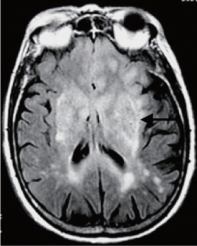

图5.15 FLAIR像示例